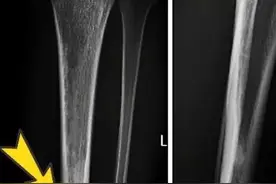

X线:一段骨干皮质增厚、硬化,大片浓白阴影,骨髓腔狭窄,甚至消失。无骨质破坏区,无死骨存在,非急性期患者周围软组织无明显肿胀。与正常骨质无明显界限,无骨膜掀起及葱皮样改变等特点(图2);

CT:髓腔狭窄或封闭,可发现普通X线片难以辨别的小透亮区(图3)。